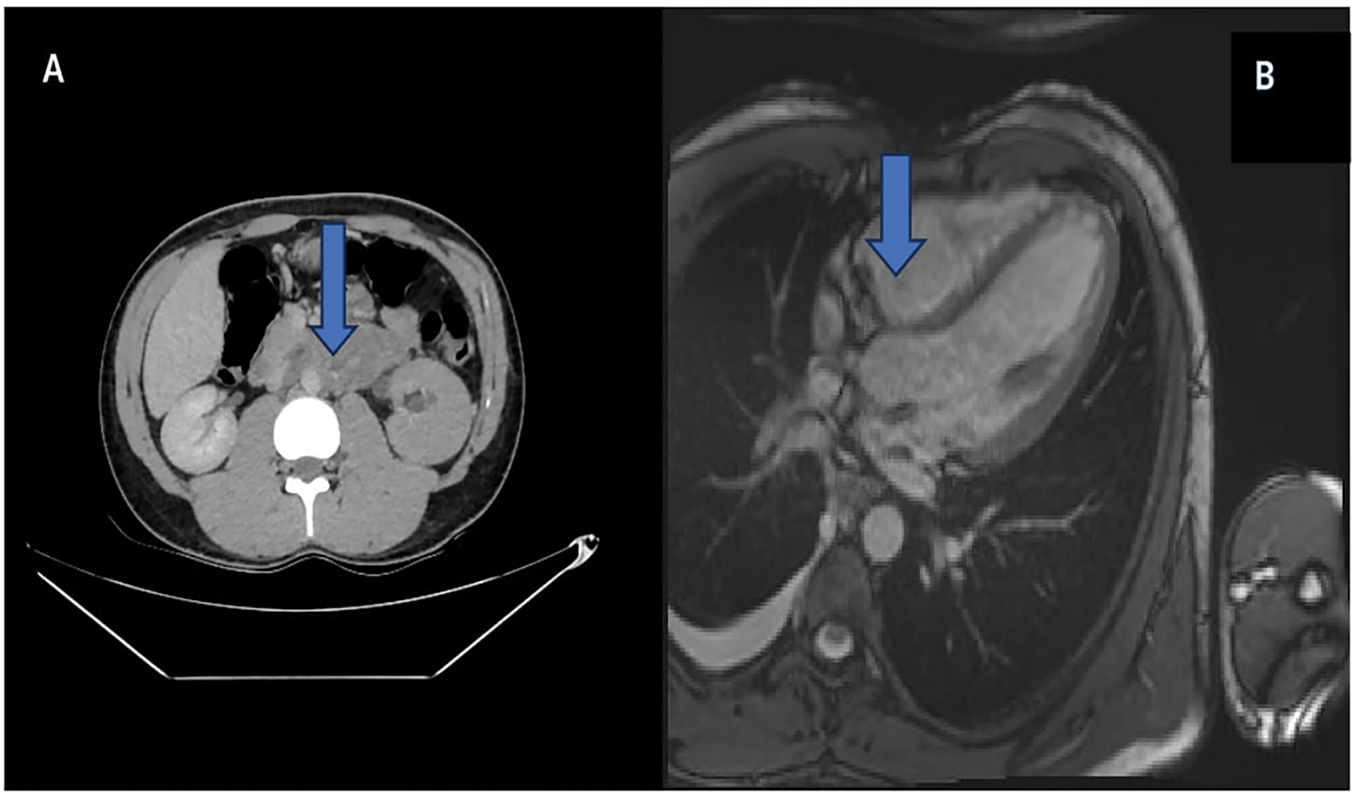

A 19-year-old male presented with a painless right scrotal mass persisting for three weeks. Physical examination revealed a firm, non-tender, 10 cm intratesticular mass. β-Human Chorionic Gonadotropin (β-HCG) was elevated (290 IU/L), while alpha-fetoprotein (AFP) and lactate dehydrogenase (LDH) were within normal ranges. Scrotal Doppler ultrasonography and contrast-enhanced thoracoabdominal CT revealed a 10 cm right testicular mass, an 8 cm para-aortic lymphadenopathy, a 3 cm pulmonary metastasis, and posterior mediastinal lymphadenopathy (Figure 1).

FIGURE 1. Metastasis of testicular tumor. (A) Para-aortic lymph node metastasis of testicular tumor on contrast-enhanced abdominal-pelvic computed tomography (CT). (B) Right atrium posterior metastasis of testicular tumor on contrast-enhanced cardiac magnetic resonance imaging (MRI) (shown with blue arrow, respectively)

The patient underwent right inguinal orchiectomy, and pathology showed 60% teratoma, 30% yolk sac tumor, and 10% embryonal carcinoma. Pre-chemotherapy transthoracic-echo-cardiography revealed a 2 cm hypoechoic mass in the right atrium. Despite three cycles of bleomycin, etoposide, and cisplatin (BEP) chemotherapy normalizing tumor markers, cardiac magnetic resonance imaging (MRI) confirmed a 4 × 3 cm metastatic lesion in the right atrium (Figure 1).